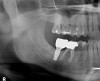

Fig 21. Panoramic image at 24 months restored.

Figure 21

Healing of the site was observed on several occasions post-surgery, including at 4.5 months (Figure 18). Excellent gingival and underlying bone contours were revealed in 24-month photographs and panoramic x-ray (Figure 19 through Figure 21).